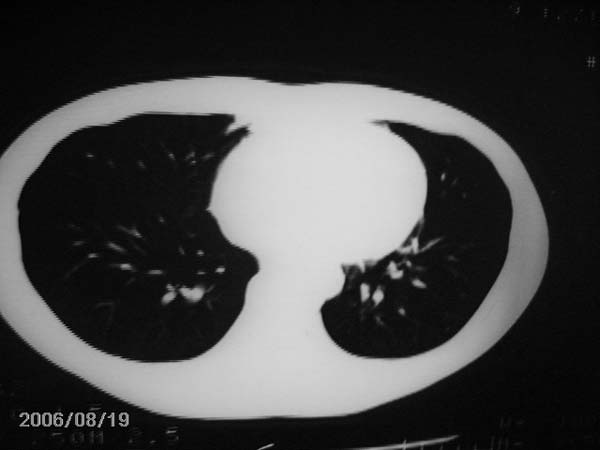

右肺结核,干酪性肺炎形成

看上去像是肺结核,让患者进一步再查查吧!

图片照得太黑了,看不太清楚。

图片还是看不太清,应尽快ppd试验及痰检,如无异常,可纤维支气管镜检排除异物可能。